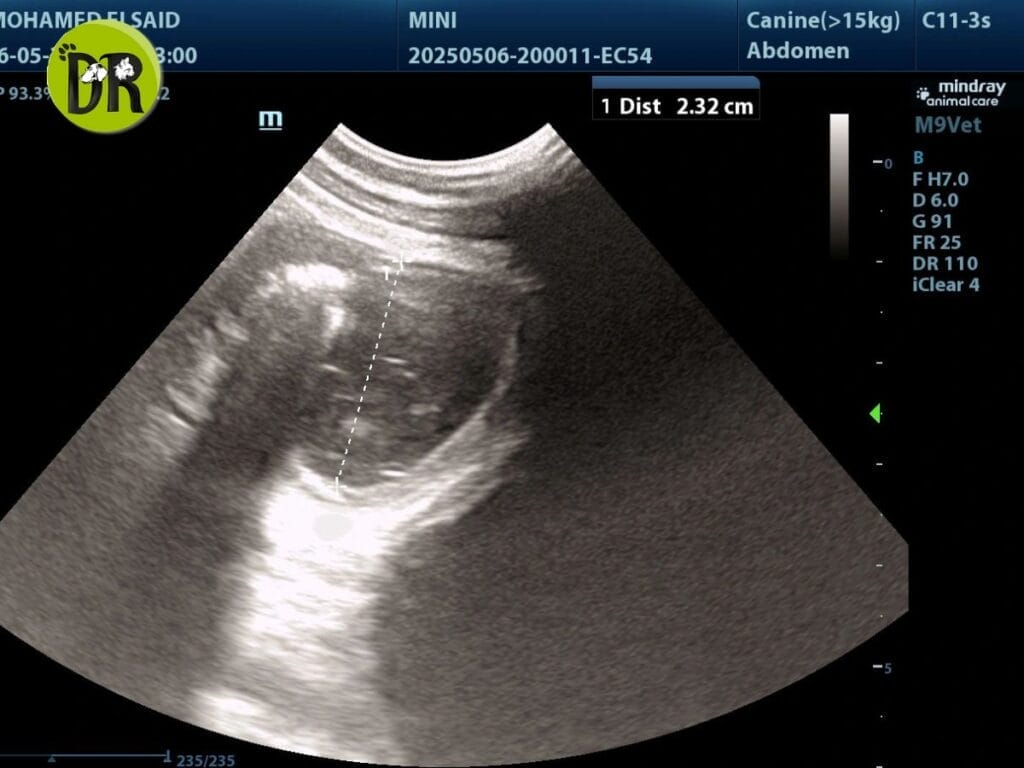

Ultrasonography showed a thickened mucosal layer of the intestinal loop and confirmed the classic ‘target lesion’, which is diagnostic for intussusception in dog. At that point, intussusception in dogs became the primary diagnosis, though we would later discover it was only part of a much larger problem